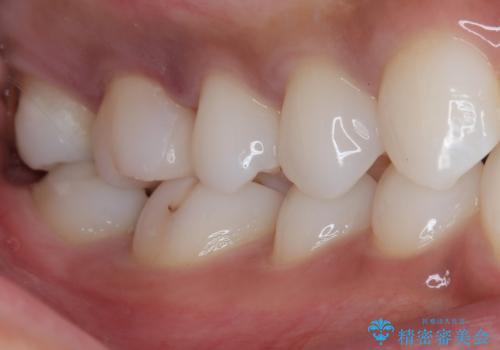

- 銀歯の詰め物が外れてしまったので、これを機にセラミックにやり替えたいと来院されれた患者様です。

虫歯になってしまっているところをしっかりと除去し、形を整えて、精度の高いシリコーンによる型どりを行いました。

また、インレー接着時には唾液や血液による接着力の低下を防ぐためにラバーダム防湿を行っています。